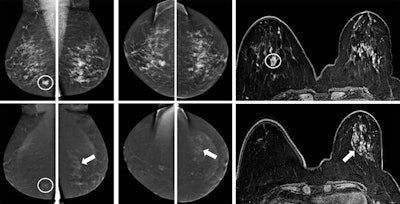

CESM is generally used in diagnostic settings with clinical indications similar to breast MRI. However, while both CESM and MRI are based on analysis of wash-in and wash-out of breast lesions, several technical differences may influence clinical performance and images interpretation, noted Dr. Clarisse Dromain, PhD, from the imaging department at Lausanne University Hospital in Switzerland, a speaker at Saturday's session. The major differences include 2D versus 3D images, contrast and temporal resolution, type and quantity of contrast agent, acquisition under compression versus free of compression, and positioning, she said.

CESM matches the performance of breast MRI, not only in terms of breast cancer detection, but also in the assessment of disease extent, explained Dr. Marc Lobbes, from the radiology department at Maastricht University Medical Center in the Netherlands. A large, prospective multicenter study conducted wi 178 patients found overall sensitivity of MRI was better than CESM (76% versus 72%), but overall specificity of CESM was better than MRI (94% versus 88%). Furthermore, CESM has fewer false positives than breast MRI, which several studies have confirmed.

"I think it is the combination between your mammographic image (in which you can appreciate the morphology of lesions very well through the high spatial resolution) and the enhancement seen on the recombined images," he told ECR Today. "On MRI, especially with small foci, you see them enhancing, but because of the spatial resolution, it is much more difficult to appreciate the subtle morphology."